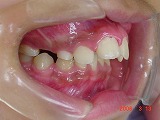

<指しゃぶりで起こるお口の変化>

<1>歯並び・顎の発育への影響

<2>口元・顔の形への影響

<3>発音・お口の機能面への影響